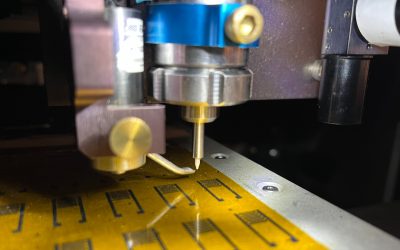

Scientists invent artificial neurons that ‘talk’ to real brain cells, paving way to better brain implants

**Breakthrough in Bio-Integrated Computing: Artificial Neurons Successfully Communicate with Living Brain Cells** In a significant leap forward for neurotechnology, engineers have developed and successfully tested microscopic, artificial neurons capable of interacting...